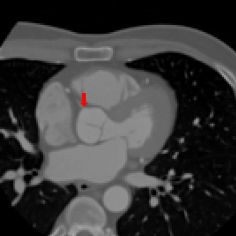

Finally, the proposed network was evaluated for the detection of five additional landmarks: the left coronary ostium, the bifurcation of the LM into the LAD and the LCx, and the origin of the left, non-coronary, and right aortic valve commissures (see Fig. 2). Fig 3 shows vector fields visualizing the predicted displacement vectors in three viewing planes in an image from the test set (for more results, see Appendix). Table 3 lists the Euclidean distance errors between the predicted landmark locations and the reference landmark locations. In addition, box-and-whiskers plots are shown in Fig 4. The best results were obtained for the origin of the right aortic valve commissure. Detection of the origin of the left aortic valve had the most narrow distribution. Outliers were seen during detection of the right ostium, the bifurcation of the LM, and the origin of the non-coronary, and the left aortic valve commissure.

Figure 2: Axial slices from a CCTA scan, resized to an isotropic voxel size of 1.5 mm, in which reference landmark locations are indicated with a colored arrow. The landmarks shown are the left coronary ostium (left), the bifurcation of the LM in the LAD and the LCx (middle left), the right coronary ostium (middle right), and the origin of the right (yellow arrow), non-coronary (red arrow) and left (blue arrow) aortic valve commissure (right).